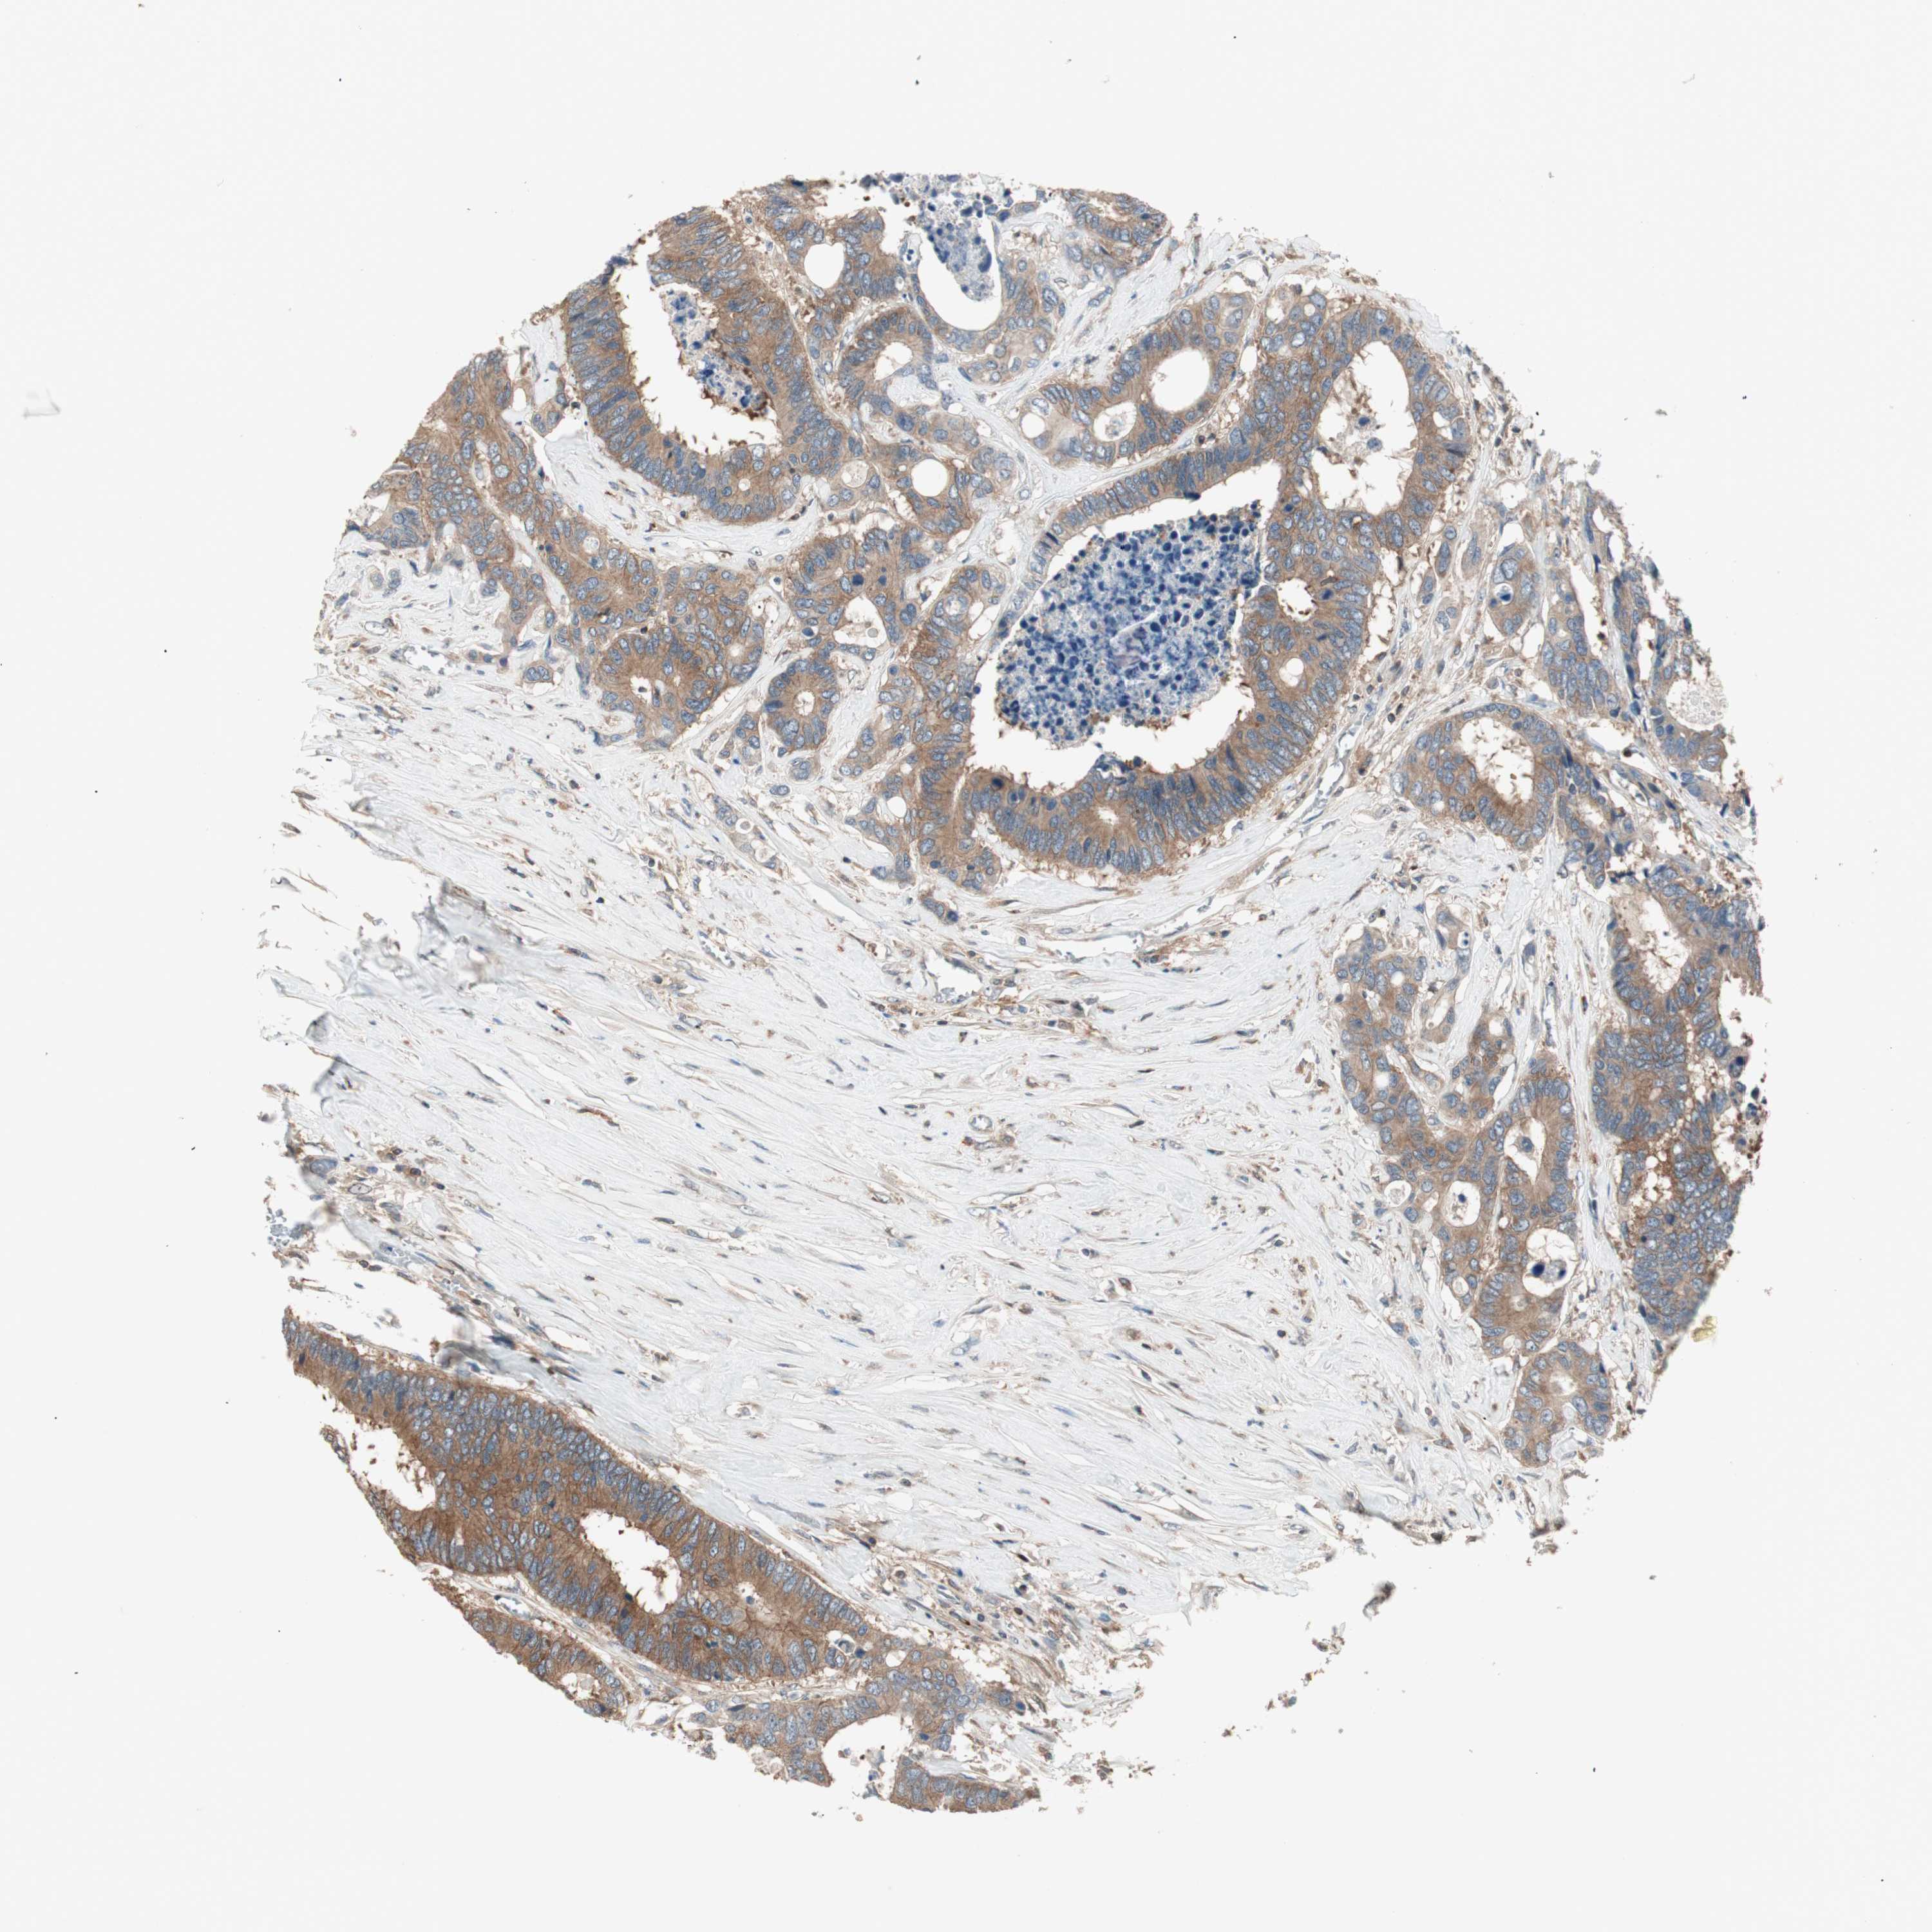

CANCER COLORECTAL CANCER Show tissue menu

Colorectal cancer

Human cancer

Colon adenocarcinoma